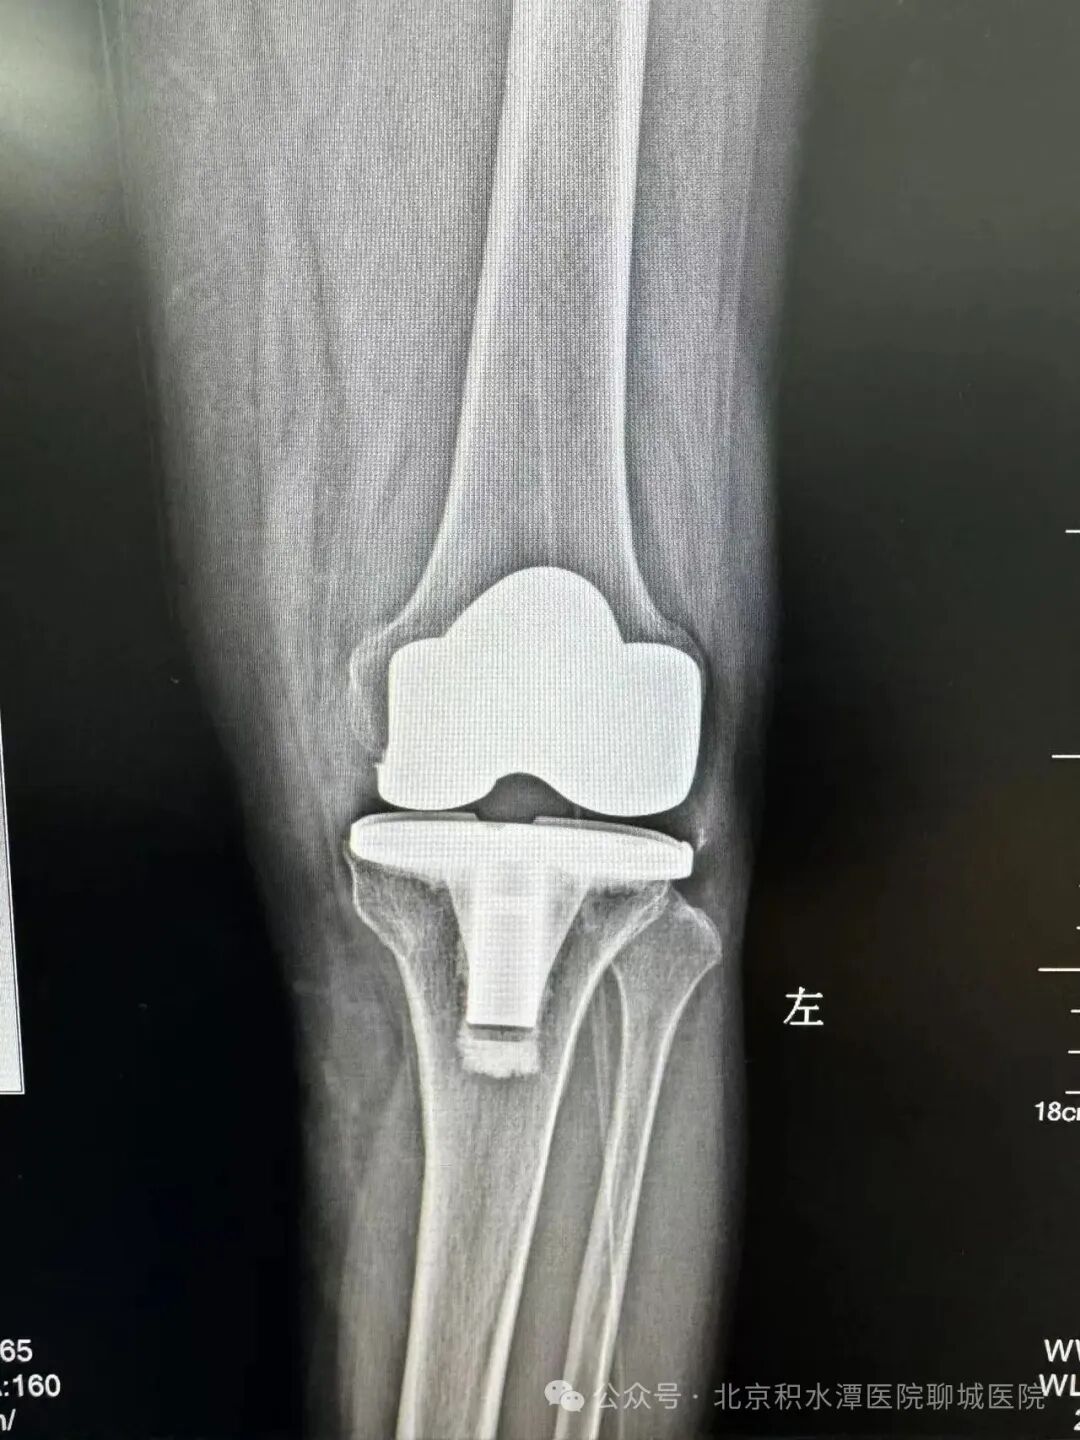

(术后影像)

基于对“隐匿性关节不稳”的清晰认知,徐辉教授团队制定了科学且极具突破性的手术方案,在保留患者自身骨量的同时,精准移除失效部件,并创新性地采用非水泥生物型假体固定技术(聊城首例)。该技术依靠假体表面特殊的生物活性涂层,诱导患者自身骨组织在术后长入假体微孔,实现更持久、更稳固的生物学骨整合,相较于传统骨水泥固定,尤其适用于翻修病例中骨条件相对较好的患者,大大提升了假体的长期稳定性。同时,手术选用了先进的“旋转平台型聚乙烯衬垫”,这一设计允许衬垫在金属底座上发生生理性旋转,显著降低了假体间的剪切应力和聚乙烯磨损,进一步提高了关节的包容性和稳定性,有效降低了远期再松动的风险。

这台融合了创新技术与精准判断的复杂翻修手术取得了圆满成功,术中出血少、创伤小。术后,在快速康复方案的指导下,患者恢复顺利,困扰她半年之久的肿痛彻底消失,关节稳定性与活动度得到显著改善。患者激动地表示:“跑了那么多地方都说‘没问题’,徐院长一检查就找到了病根!手术做完就不疼了,太感谢徐院长和积水潭聊城医院了!”